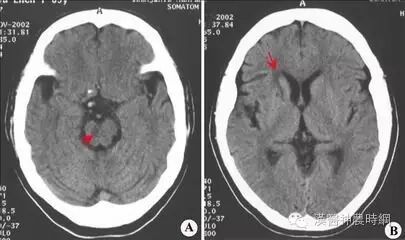

心梗脑梗竟和早餐有关!并不是危言耸听!

心梗和脑梗,是尽人皆知的威胁我们健康的两种疾病。但是,很多人不知道,这两种疾病的发生,竟和现代人对早饭的忽视有关系。

不吃早饭,胃中就缺少食物,人体血液里就会形成很多的B型血栓球蛋白。这是一种能导致血液凝固,使人易患心肌梗塞的蛋白质。不吃早饭的人,血小板比吃早饭的人更加容易粘稠与聚集。这就加大了血栓的形成几率,使人更加容易患上脑梗和心梗。

不吃早饭,致动脉硬化、心梗脑梗

专家认为,长期不吃早饭,容易使低密度脂蛋白沉积于血管内壁,导致动脉硬化的发生。

另外,有科学家曾对长期不吃早饭的人群进行过详细研究,发现其患心肌梗塞、脑梗等病症的几率也比正常进食早饭的人群高出许多。